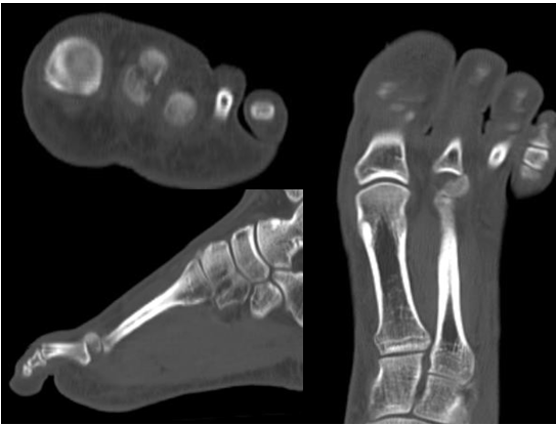

A 19-year-old male presented at our emergency department with a history of left foot trauma when landing from a jump, with the toes in hyperextension. He reported immediate onset of acute pain and inability to perform weight bearing as well as dorsal swelling over the second metatarsophalangeal joint. He denied any significant past medical history or any current medications. Physical examination revealed swelling, bruising and pain over the left second metatarsal head. He presented painful mobilization of the second metatarsophalangeal joint as well as crepitation on palpation and had no neurovascular impairment. Plain radiographs, with oblique and anteroposterior views, of the left foot revealed an osteochondral fracture of the second metatarsal head (Figure 1). Due to the nature of the lesion and fracture pattern, a CT scan was preformed, showing a slipped retroverted osteochondral fragment (Figure 2).

Figure 1: (a) Anteroposterior and

(b) Oblique plain radiographs of the left foot showing

the osteochondral fracture of the second metatarsal head.